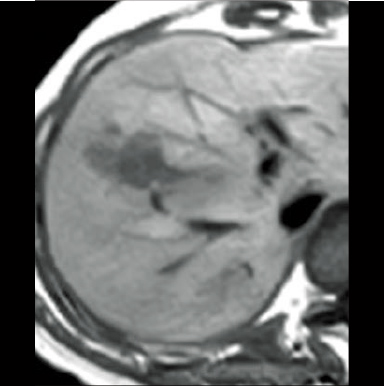

T1WI